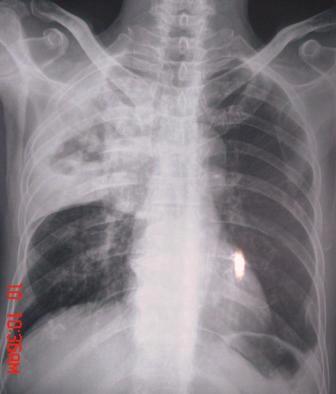

xx 男 63岁 发热 家属描述有时高热 有时低热 抗酸杆菌阴性 于2月21号 胸片及ct

3月10号复查

楼主  :谢谢大家发言  我和大家考虑的一样干酪性肺炎并播散